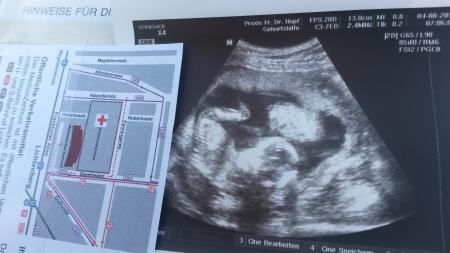

Bauchzwerg fühlt sich ersichtlich pudelwohl in meinem Bauch.

Eigtl. wollten wir uns überraschen lassen aber mein Sohn fragte prompt nach ,ob er eine Schwester oder einen Bruder bekommt... ..und ich habe im Ultraschall die Kaffeebohne gesehen. Ärztin meinte 80% ein Mädchen

Baby liegt auf dem Rücken. .kinn auf die Brust,Po nach oben und die Beinchen sind angewinkelt :) -->> siehe Bildchen ♡♥